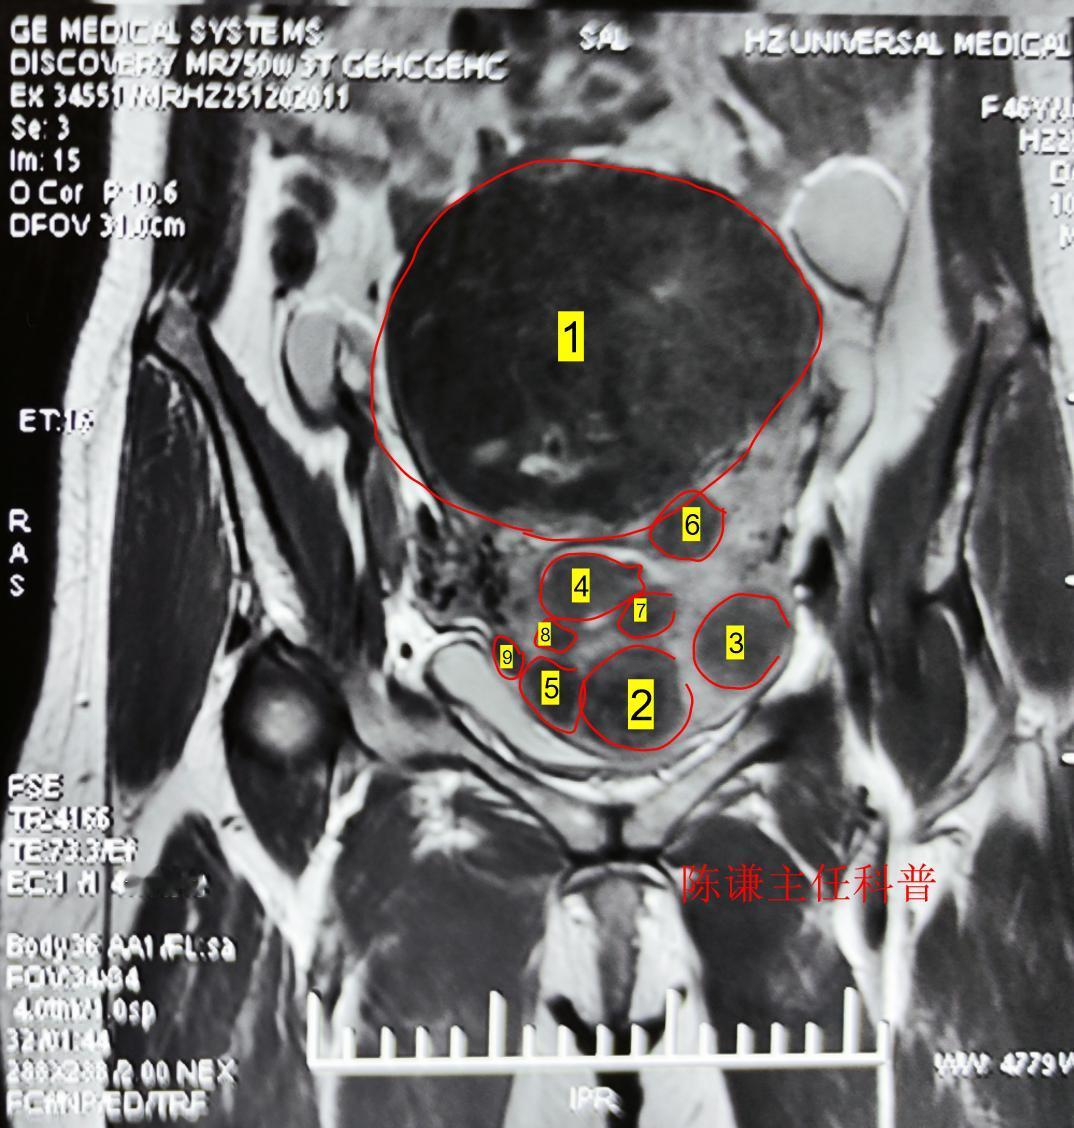

这是我们才治疗的一名多发性子宫肌瘤患者,患者来自上海,发现肌瘤有近10年了,患者

这是我们2个月前海扶刀治疗的一名多发性子宫肌瘤患者,病人最大肌瘤9.8cm,血流